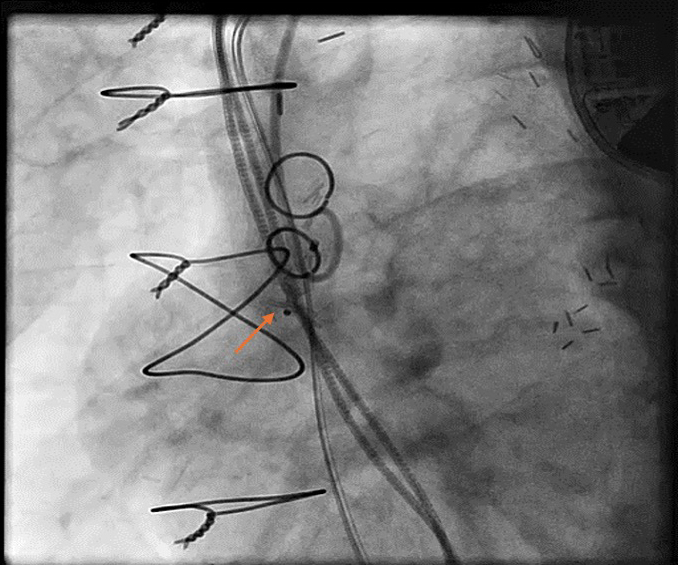

Figure 2

Figure 2. Aneurysm shape is seen through the contrast.